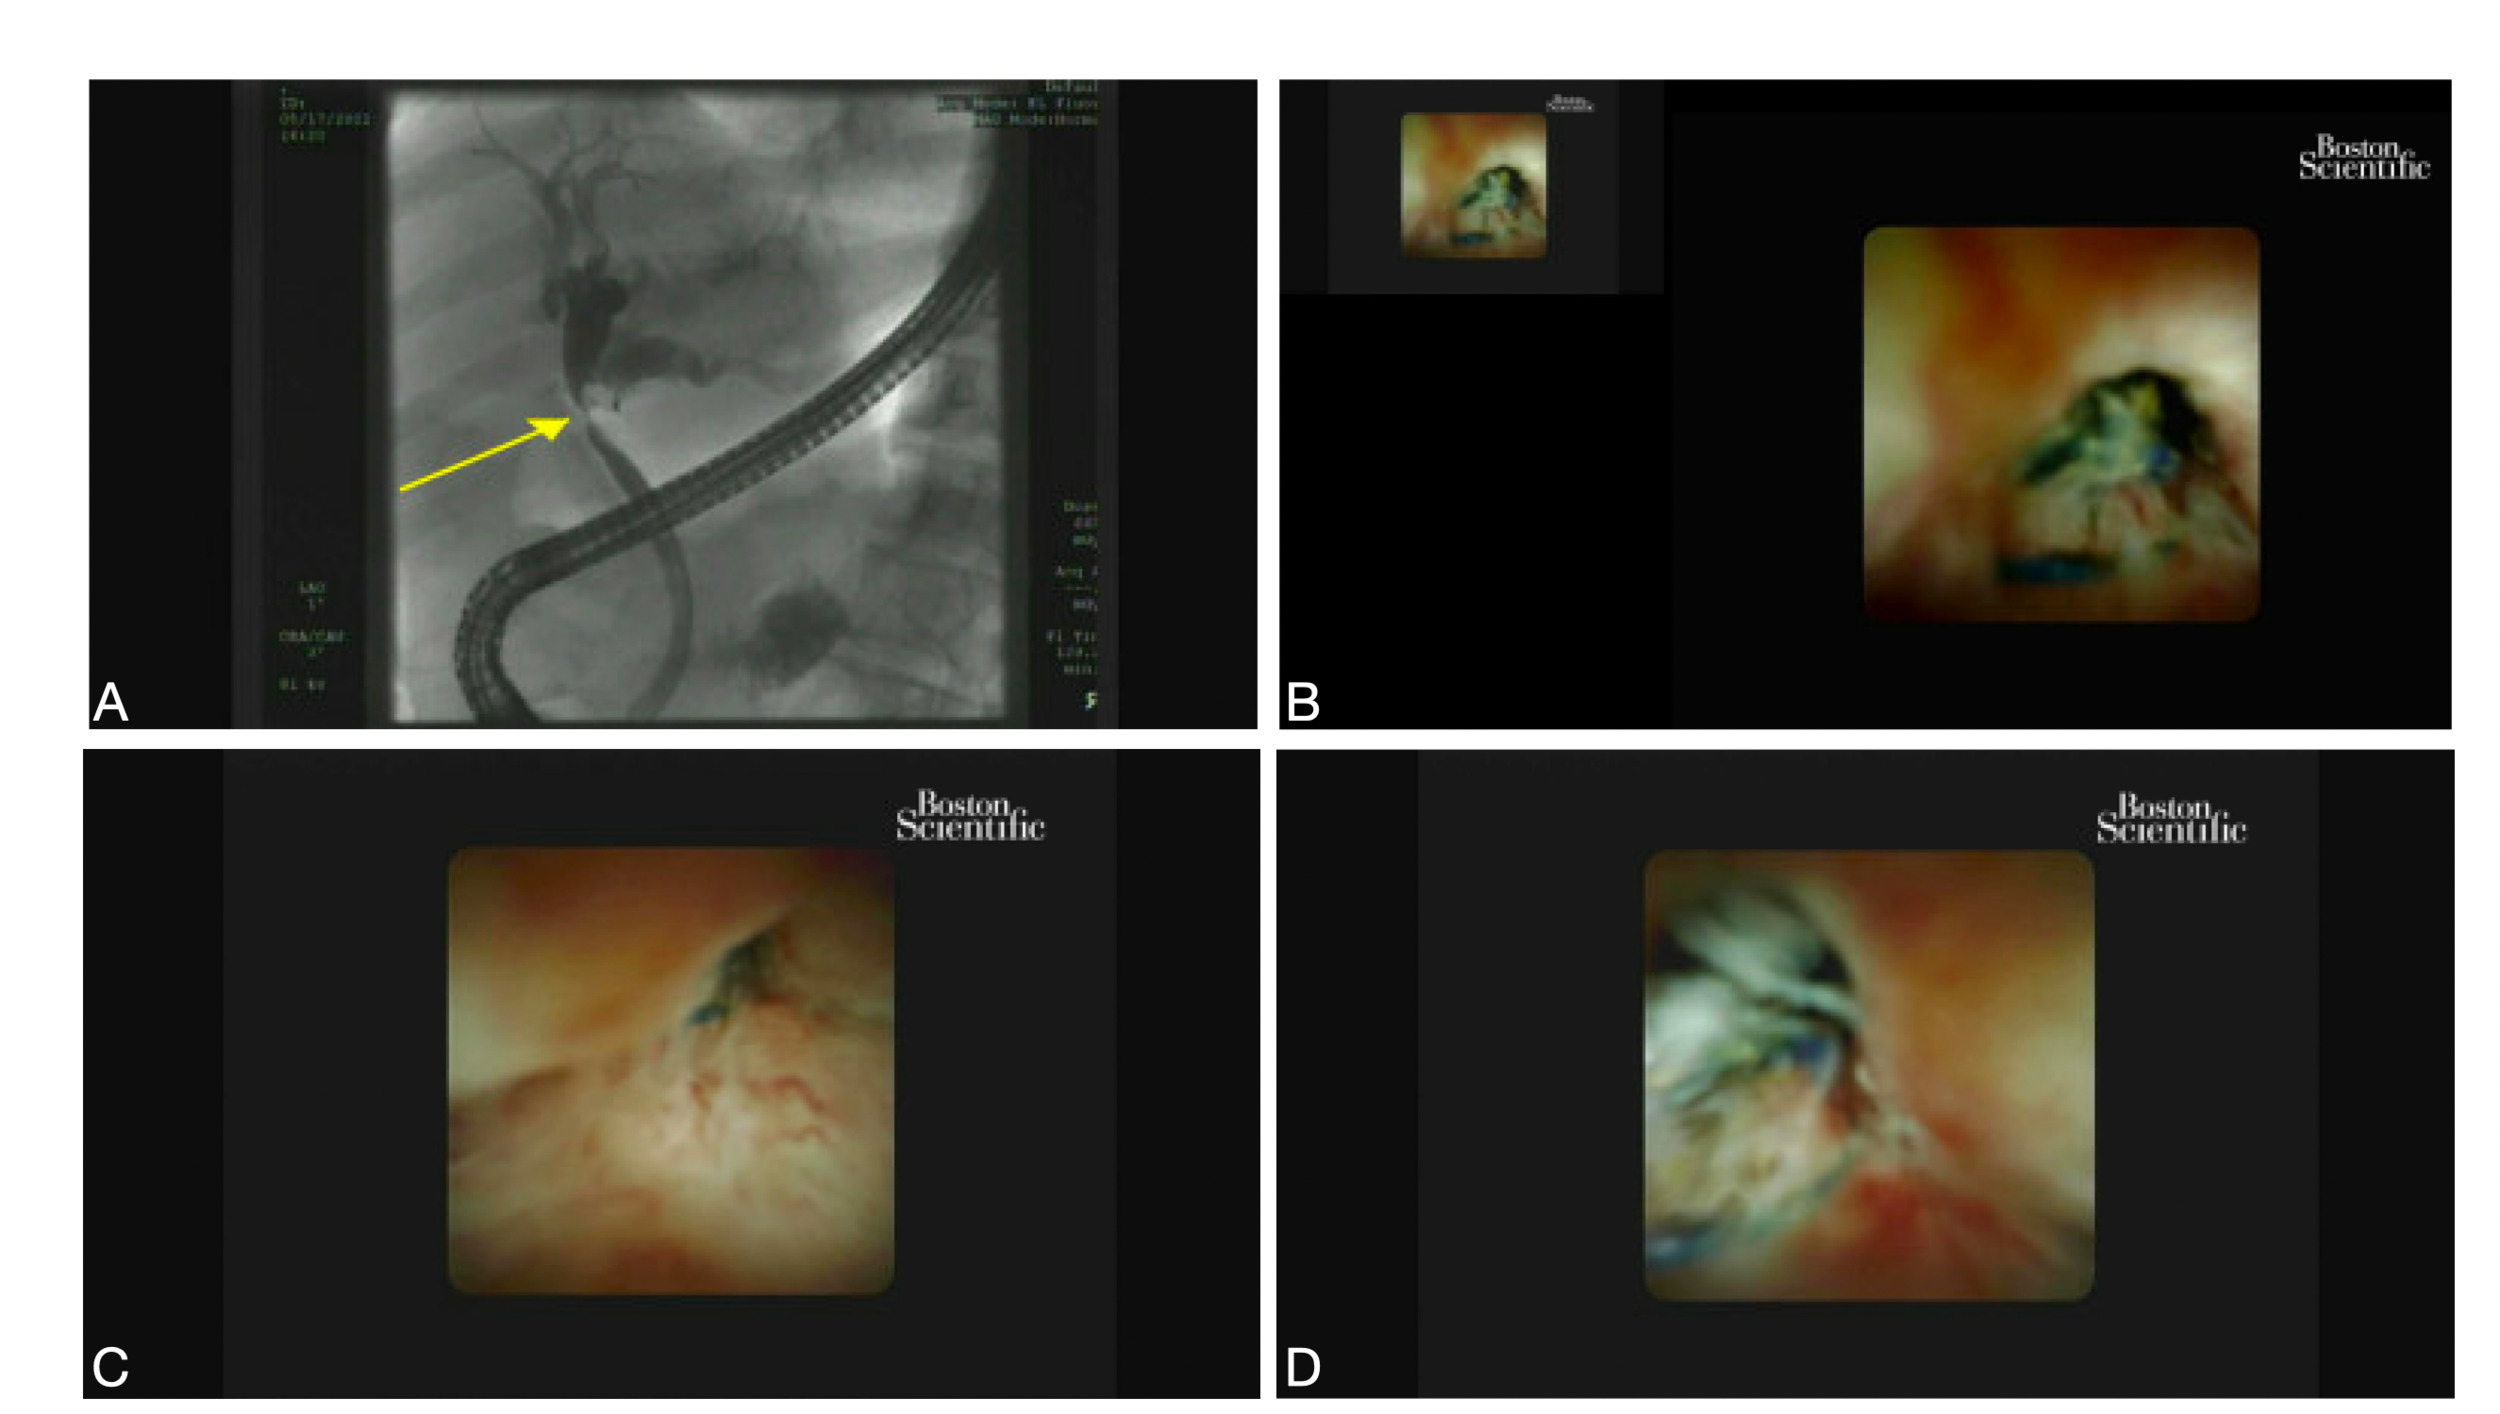

A 76-year-old man with a past medical history of hypertension and diabetes mellitus, and a past surgical history of a laparoscopic cholecystectomy ten years prior to presentation presented to hospital for one week of jaundice, darkening of urine, and pruritus. He denied any weight loss, abdominal pain, nausea, or vomiting. Physical exam was notable for icterus, and the abdomen was soft and non-tender without any palpable masses. Laboratory evaluation was significant for a total bilirubin of 14.8 mg/dL (0.1 to 1.2mg/dL), direct bilirubin of 7.6 mg/dL (0.3 mg/dL) , AST 40 U/L (8 to 33 U/L), ALT 56 U/L (4 to 36 U/L), and alkaline phosphatase of 128 U/L ( 44 to 147 U/L). MRCP was obtained, which showed a poorly defined soft tissue lesion at the common hepatic duct (CHD) with intrahepatic ductal (IHD) dilation. The patient was referred for EUS and endoscopic retrograde cholangiopancreatography (ERCP) for further evaluation. EUS revealed IHD dilation and a benign appearing porta hepatis lymph node without endosonographic evidence of pancreatic mass or cysts. The lymph node at the porta hepatis was sampled using fine needle aspiration (FNA). ERCP was then performed, revealing a single stenosis at the level of the CHD with upstream dilation suggestive of malignancy, shown in Figure 1, Image A. Cholangioscopy was performed, which showed an inflammatory-appearing stenosis of the CHD with embedded suture material (Figure 1, Images. B, C &D). The stenosis was biopsied using mini forceps and subsequently dilated with a balloon dilator. An 8.5 Fr x 10 cm Advantix™ (Boston Scientific, Marlborough, MA) plastic biliary stent was placed with subsequent improvement in the patient’s hepatic function. FNA cytology and final pathology of the CHD stricture were both negative for malignancy.